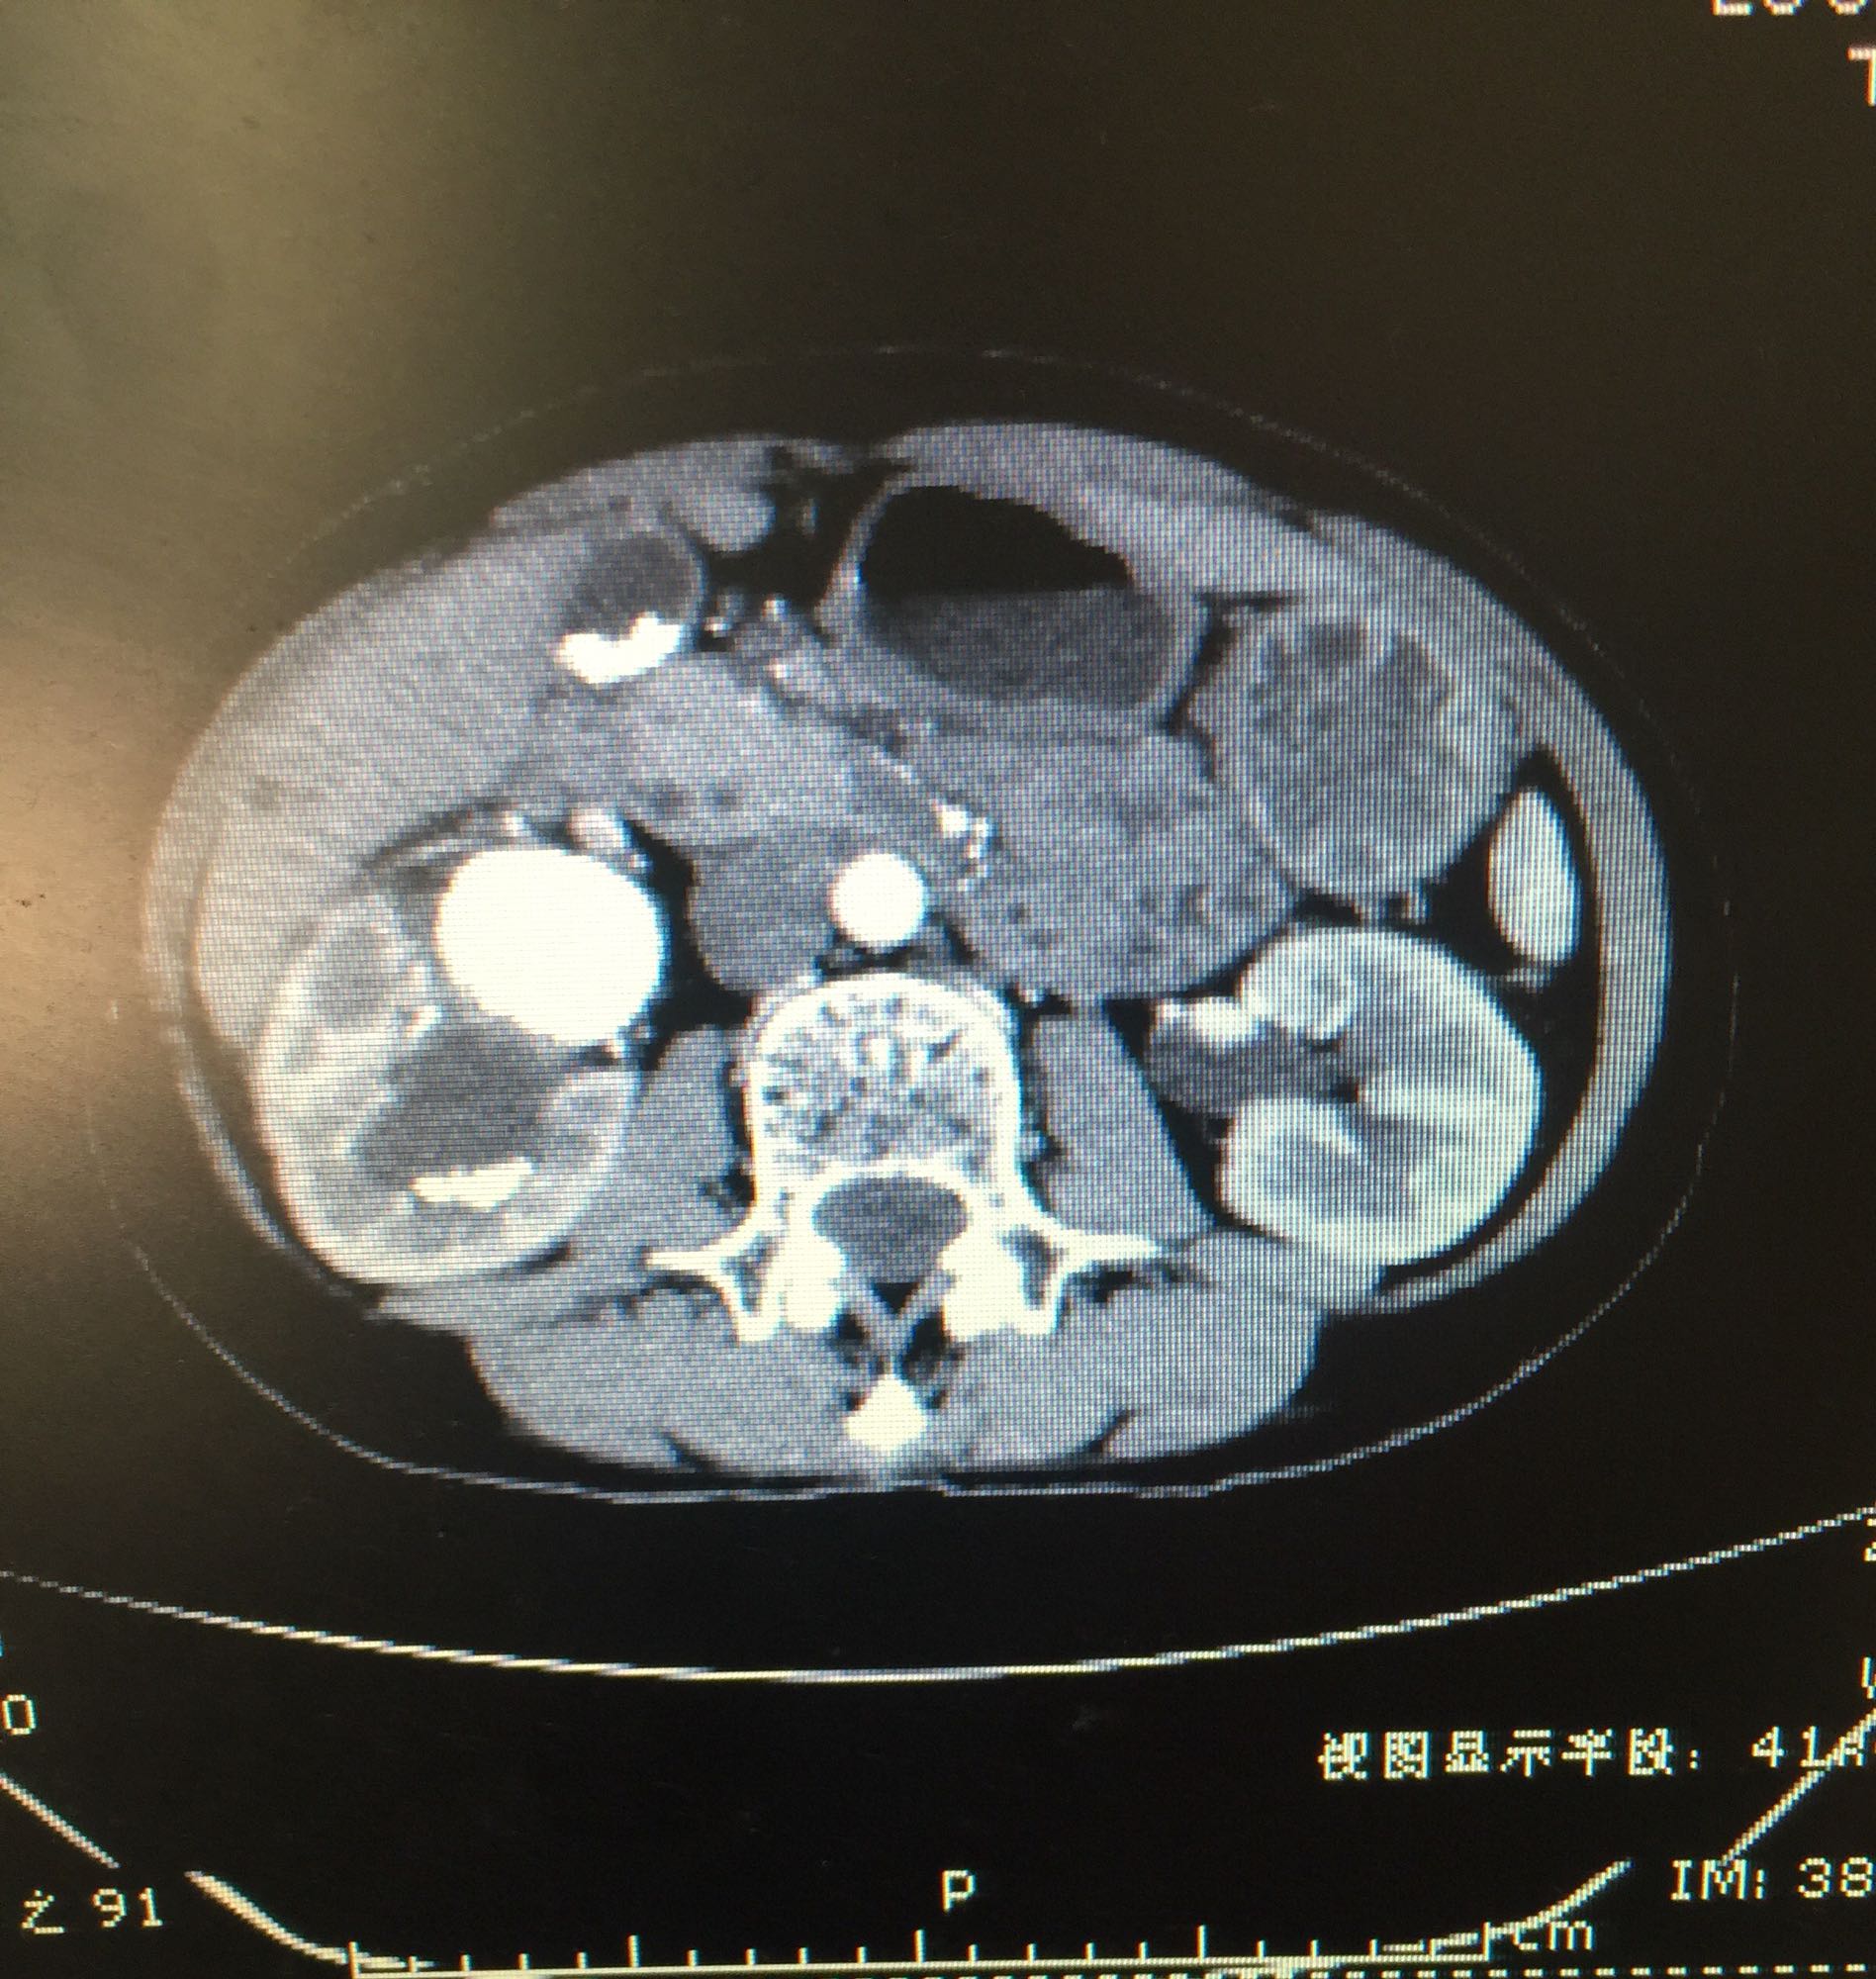

右侧肾脏巨大铸型结石一例

肾盂积水伴输尿管肾盂连接处梗阻 肾结石

60余岁老年男性 因右侧腰痛伴发热1周入院 1周前开始出现右侧腰部胀痛,伴低热,无尿频尿急及肉眼血尿,无其他不适症状 既往高血压,无糖尿病及其他病史

查体右侧肾区轻度叩痛,余症状阴性 辅助检查尿白细胞+++,肾功正常,甲状旁腺激素正常,钙磷比例正常范围

右侧肾脏巨大铸型结石,右肾盂输尿管连接部狭窄? 拟完善GFR测定后决定下一步治疗方案,目前倾向于开放手术。

该患者结石大,且负荷大部分位于肾盂,肾盂几乎被填满,所以考虑是否有右侧输尿管肾盂连接部狭窄可能,结石负荷大,结合上述情况可行开放手术,一期整形 。 但若为UPJO,患者肾脏积水轻,肾脏皮质厚,肾功影响小,可能性相对小。行PCN结合超声吸附,一期清理肾盂内结石应该问题不大。 对于该患者的治疗,不知大家意见如何?